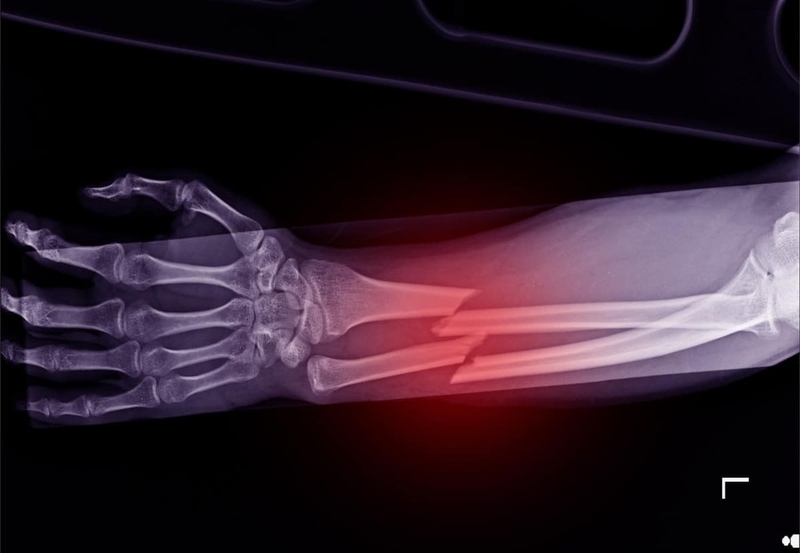

Khi xương bị gãy kèm theo tình trạng di lệch thì các đầu xương cũng bị lệch ra ngoài. Đối với trường hợp này, bác sĩ sẽ nắn xương bị lệch lại cho thẳng hàng. Sau đó, phần xương bị tổn thương sẽ được cố định lại bằng nẹp hoặc bó bột để xương lành lại. Nếu phương pháp này không thành công thì bác sĩ sẽ tiến hành điều trị thêm bằng phương pháp khác.

Nếu gãy xương có di lệch ra khỏi vị trí ban đầu, bác sĩ sẽ tiến hành phẫu thuật cho người bệnh để di chuyển xương bị gãy trở lại vị trí giải phẫu ban đầu. Cuộc phẫu thuật này được tiến hành tại khoa cấp cứu hoặc phòng phẫu thuật và người bệnh cần được an thần hoặc gây mê toàn thân, sau đó có thể bó bột toàn bộ nhằm hỗ trợ quá trình lành vết thương.

Tuy nhiên, trong quá trình phẫu thuật có thể không tránh khỏi một số tai biến như gãy hở, sock, chèn ép khung hoặc tím tái do bó bột quá chặt. Những biến chứng này có thể gây ra tình trạng rối loạn dinh dưỡng hoặc hội chứng Volkman và biến chứng muộn có thể gặp như vẹo trục xương, can lệch xương, liệt thần kinh, viêm xương, khớp giả, đầu sụn hoặc tiêu chỏm,…